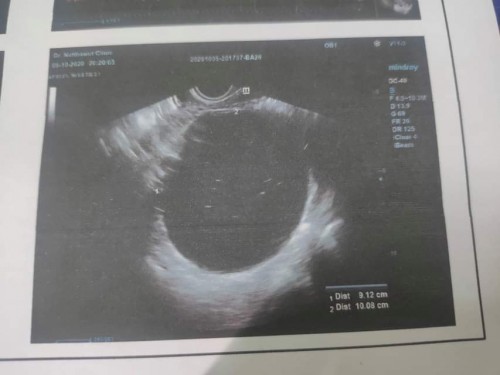

วันนี้ไปฝากครรภ์มาค่ะ 8w 6d หมอตรวจพบ ก้อนถุงน้ำในรังไข่ขนาดใหญ่มากจนหมอร้อง โอ้พระเจ้า😭😭😭10เซน หมอบอกพร้อมจะแตกแตกตลอดเวลา หมอไม่ฟันธงว่า จะไม่ใช่เนื้อร้าย 😖😖